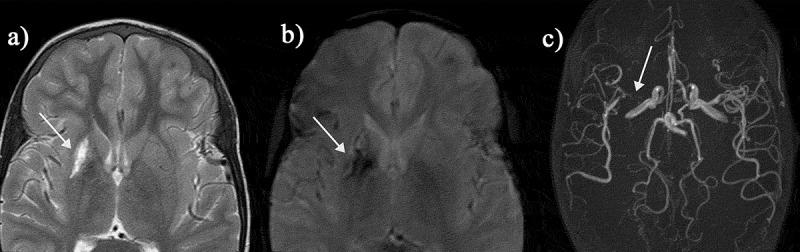

: Over the past decades, neuroimaging studies have clarified that a significant proportion of patients with sickle cell disease (SCD) have functionally significant brain abnormalities. Clinically, structural magnetic resonance imaging (MRI) sequences (T2, FLAIR, diffusion-weighted imaging) have been used by radiologists to diagnose chronic and acute cerebral infarction (both overt and clinically silent), while magnetic resonance angiography and venography have been used to diagnose arteriopathy and venous thrombosis. In research settings, imaging scientists are increasingly applying quantitative techniques to shine further light on underlying mechanisms.: From a June 2020 PubMed search of 'magnetic' or 'MRI' and 'sickle' over the previous 5 years, we selected manuscripts on T1-based morphometric analysis, diffusion tensor imaging, arterial spin labeling, T2-oximetry, quantitative susceptibility, and connectivity.: Quantitative MRI techniques are identifying structural and hemodynamic biomarkers associated with risk of neurological and neurocognitive complications. A growing body of evidence suggests that these biomarkers are sensitive to change with treatments, such as blood transfusion and hydroxyurea, indicating that they may hold promise as endpoints in future randomized clinical trials of novel approaches including hemoglobin F upregulation, reduction of polymerization, and gene therapy. With further validation, such techniques may eventually also improve neurological and neurocognitive risk stratification in this vulnerable population.

在过去的几十年中,神经影像学研究已经阐明,相当一部分镰状细胞病(SCD)患者存在功能上显著的大脑异常。临床上,放射科医生使用结构磁共振成像(MRI)序列(T2、FLAIR、弥散加权成像)来诊断慢性和急性脑梗死(显性和临床无症状),而磁共振血管造影和静脉造影则用于诊断血管病变和静脉血栓形成。在研究环境中,成像科学家越来越多地应用定量技术来进一步揭示潜在的机制。